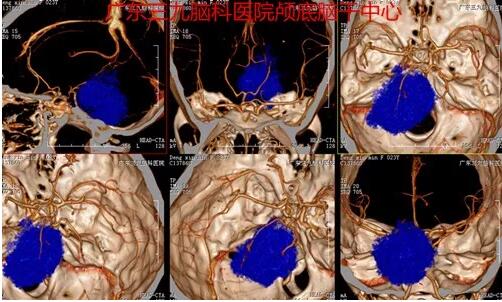

图2:2017-11-50头颅CTA示病灶内及边缘示少许细小血管影,基底动脉轻度受压右偏